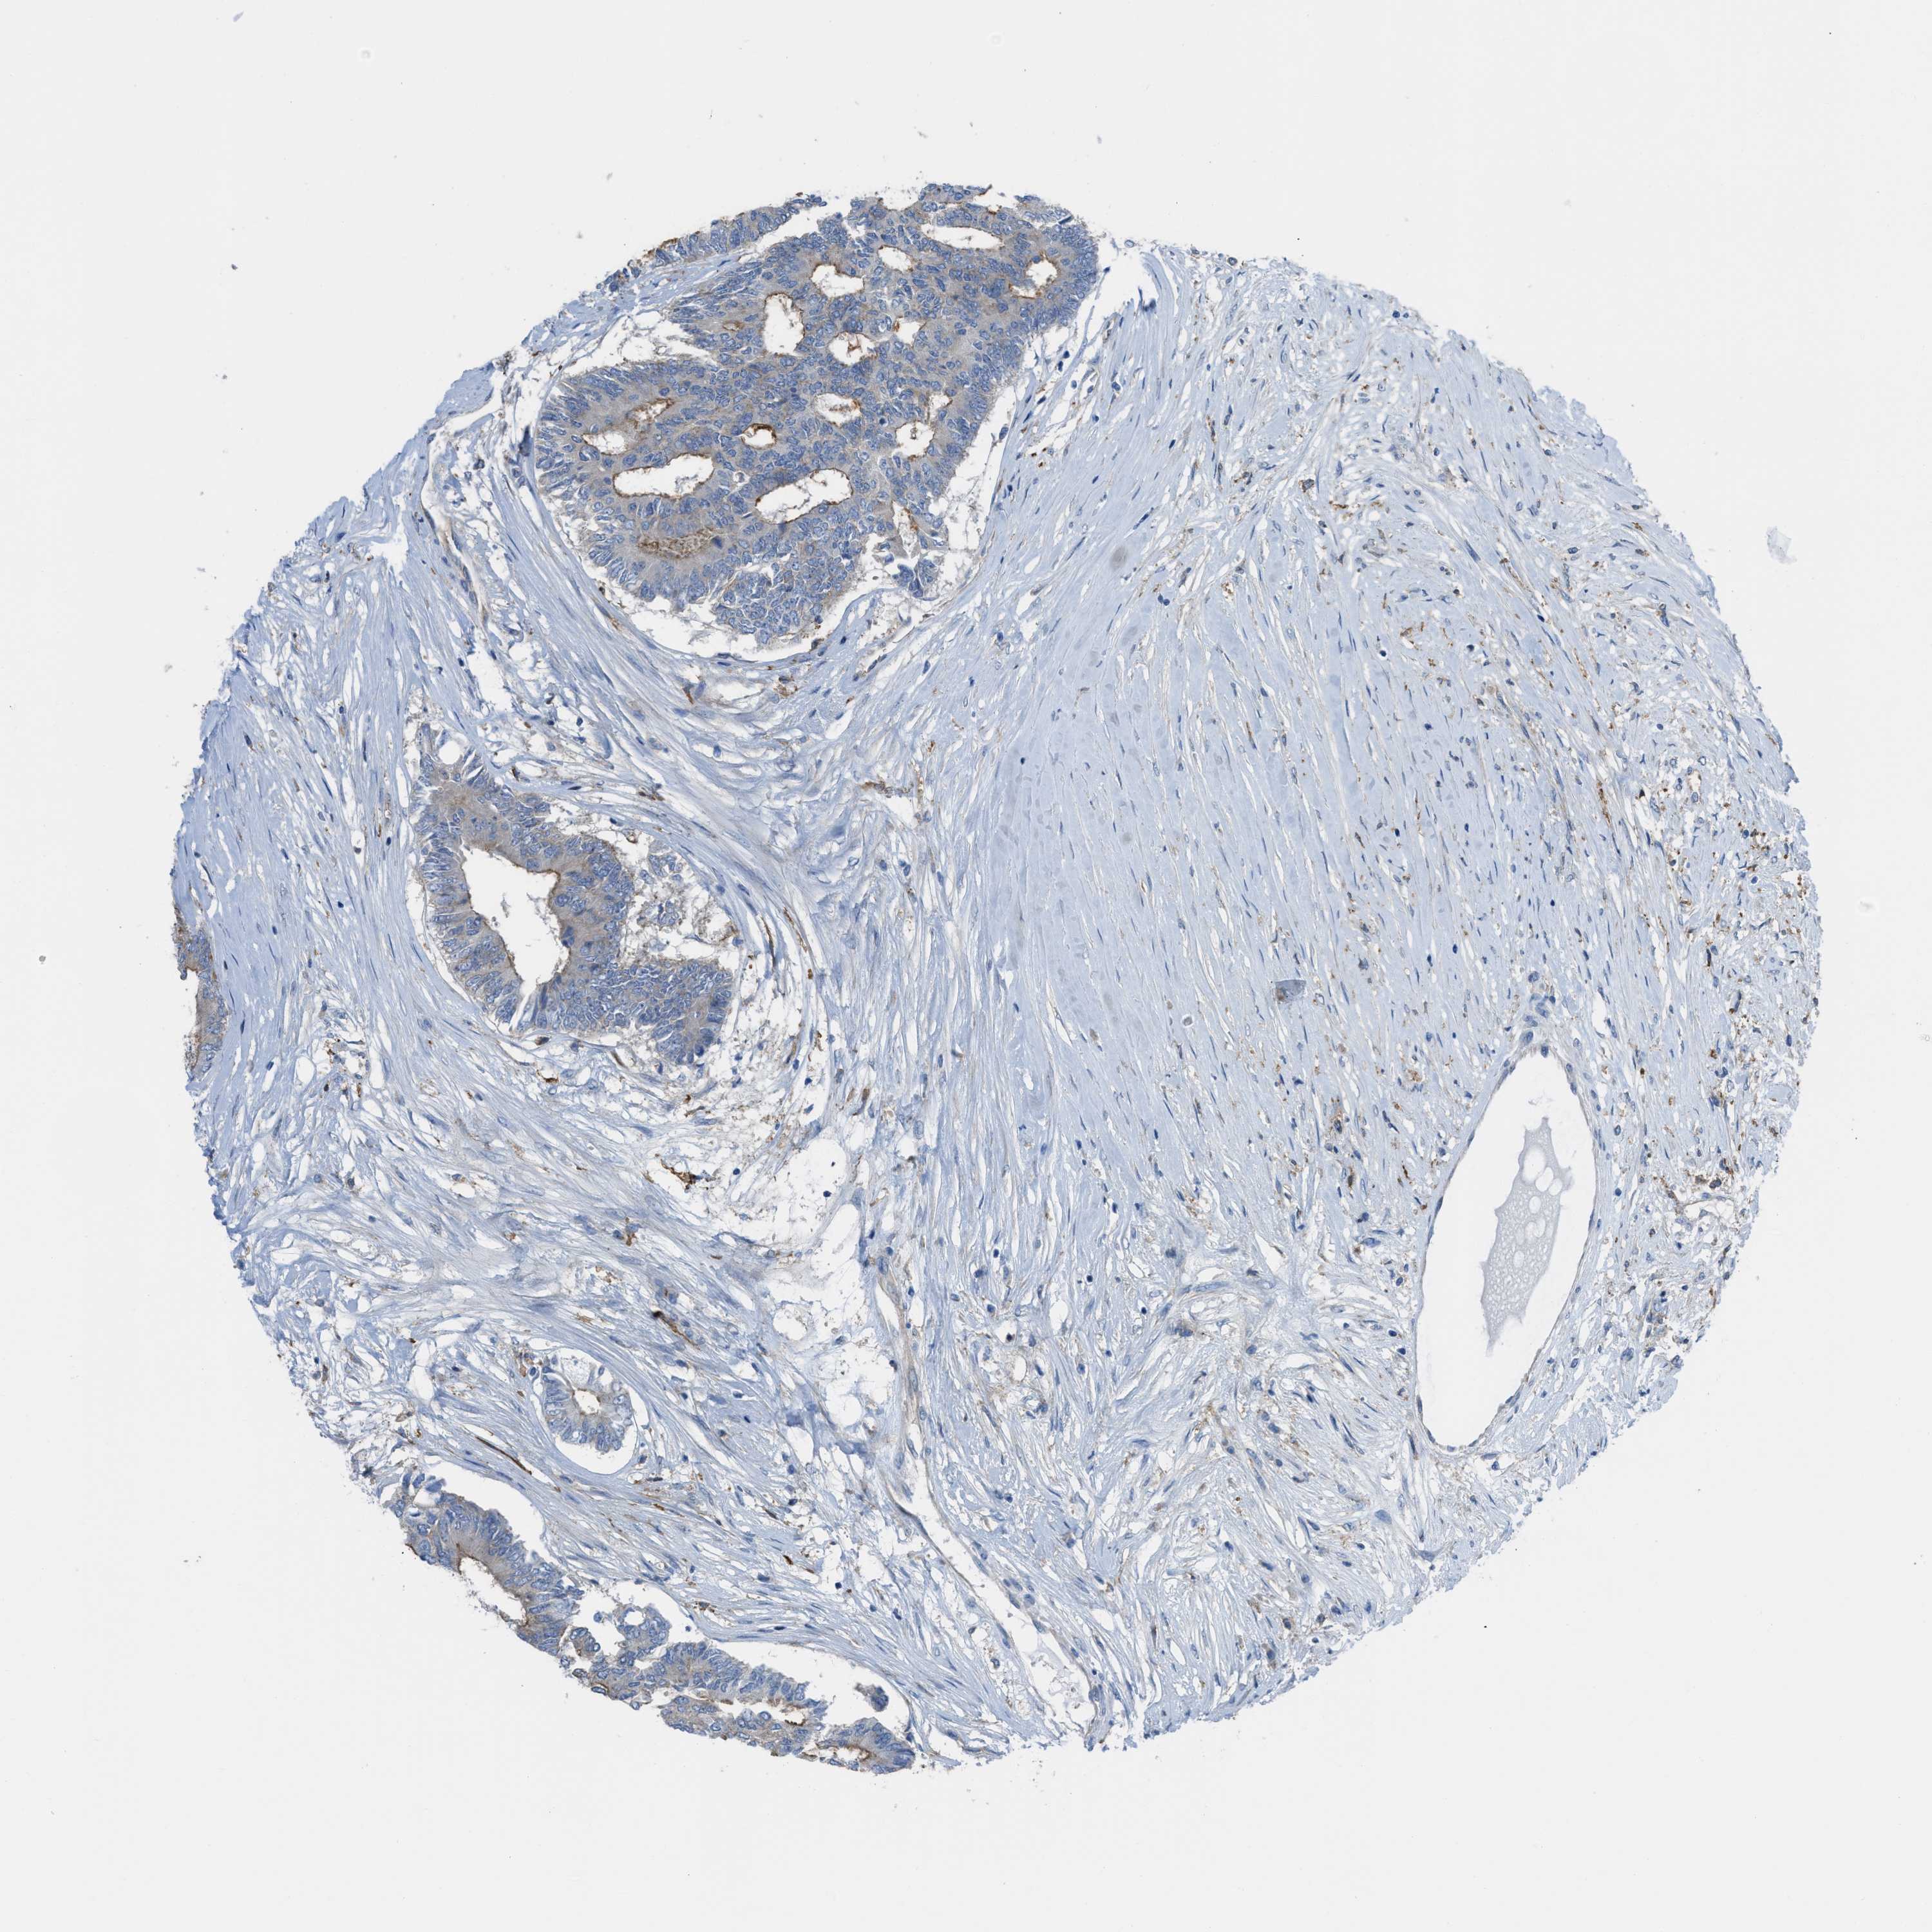

CANCER COLORECTAL CANCER Show tissue menu

Colorectal cancer

Human cancer

Colon adenocarcinoma